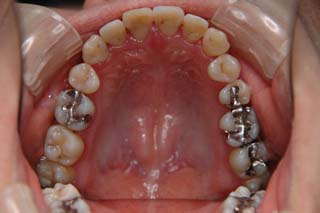

(叢生/正中変位/上右小臼歯抜歯(片顎片側抜歯)/ ハーフリンガル)

骨格的な非対称や治療前に見られた咬耗など、対処が難しい問題もありますが、前歯部被蓋、臼歯関係ともに良好です。今後、保定管理を継続する予定です。